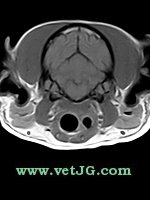

RESONANCIA MAGNÉTICA

AXIAL